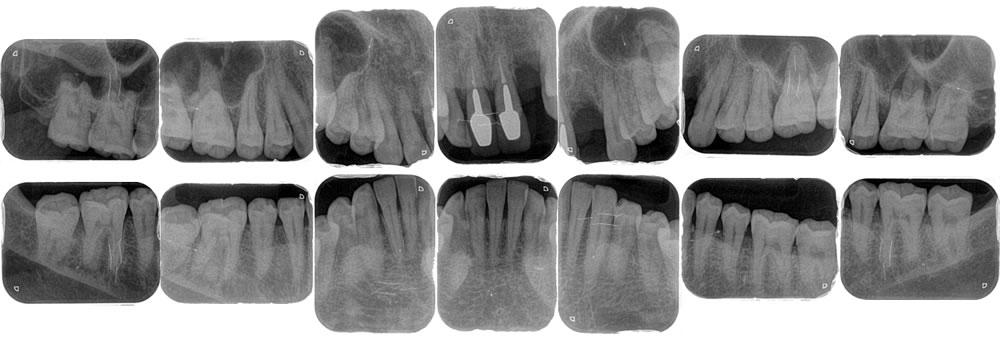

【初診時パノラマX線写真/デンタルX線写真】

各レントゲン写真から虫歯の有無、歯を支える骨の状態を細かな部分までチェックします。抜け落ちた歯の部分には骨が陥没している様子が見えました。虫歯はないようですが、周囲の歯も歯周病により支える骨が全体的に溶けている様子が確認できました。そのため、欠損部の咬み合わせを回復する前に歯周病治療を行い、口腔内の環境を改善する治療計画を立てました。